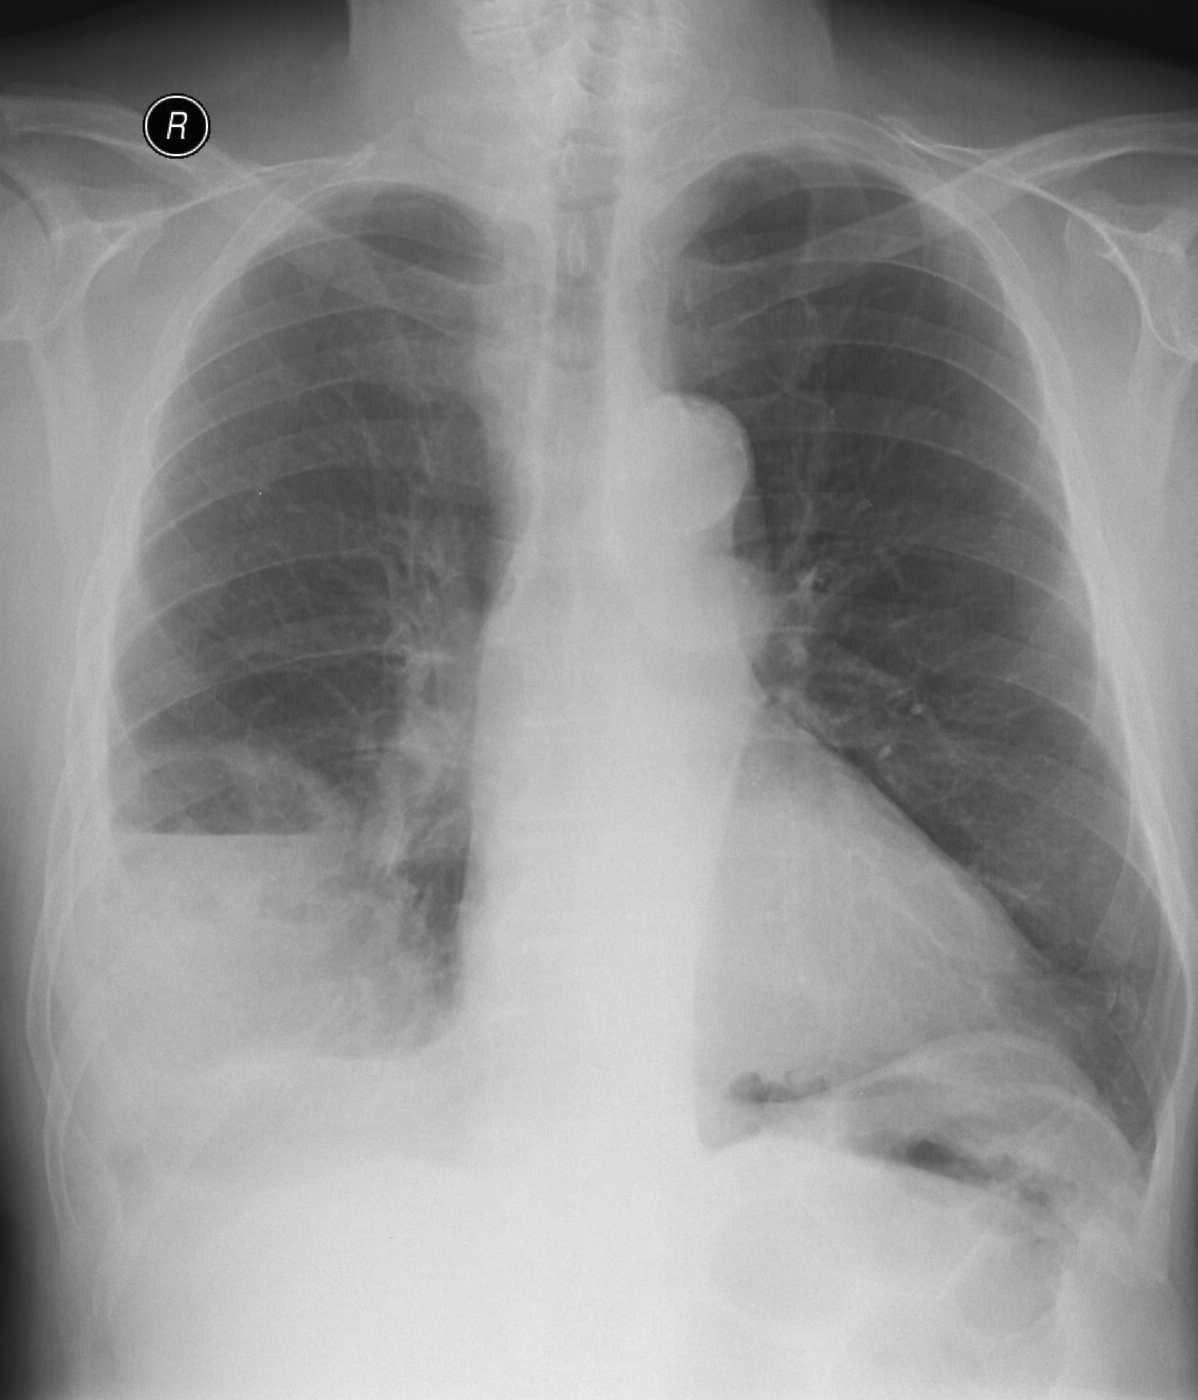

19. Tuberculosis, bidirectional chest radiographs and HRCT. (coronal reconstruction)

75 year old man: hx of hypertension, smoking. Symptoms: dyspnea, productive cough. Moist rales of auscultatory findings above the LLL, tension irritability in the level of lower dorsal spine.

a.) Chest radiograph, bilateral: Mild increased vascular markings. Extensive patchy lobar infiltration in the RUL Previous TB specific lesions in the left apex. The diaphragm contour is blurry on the right side (appr. 4 finger-wide pleural effusion). Cardiomegaly. Medium large dilated sclerotic aorta.

b.) HRCT: Reticular pattern of 10x10x5 cm area in the right apex (1st segment), (septal thickenings), mosaic-like ground glass opacity in the righ apex. Subpleural total atelectasis (mainly 1st segment): irregular mainly nodular soft tissue streak associated with the pleura (max. appr. 1 cm thickness). Some tiny subpleural emphysematous bullae in the right apex.